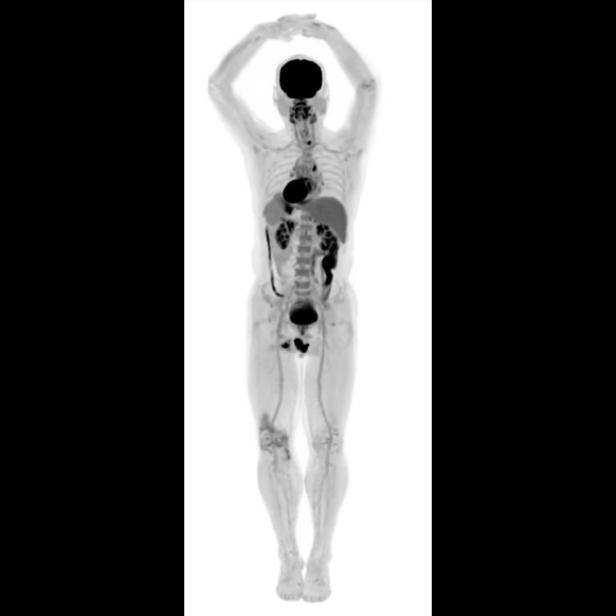

Böser Computer könnte Röntgenbilder verfälschen

Schweizer Wissenschafter zeigen die Möglichkeit auf, der Angriff sei aber noch nicht durchführbar.